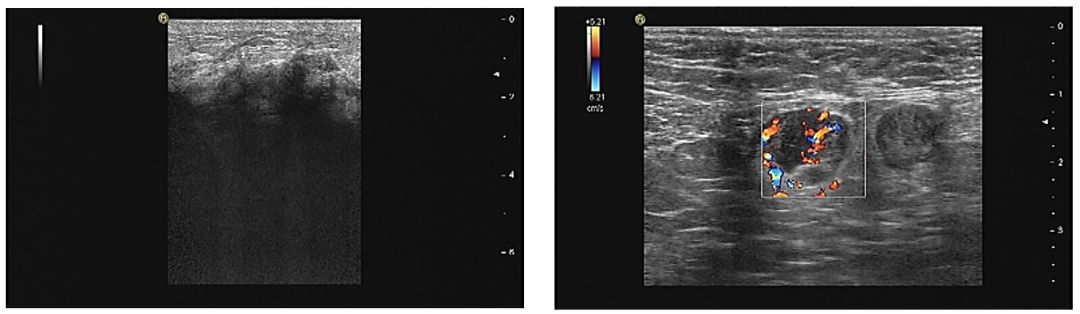

乳腺彩超提示左乳上方及外侧软组织水肿明显,上方10-3点距乳头2cm探及低回声,大小无法测量,深34 mm,形态不规则,边界不清晰,边缘毛刺,内部回声不均匀,后方回声衰减,后方胸大肌显示不清晰,彩色血流条状,RI 0.57。左侧腋下探及多个椭圆形中低回声区,大者约15*12 mm,边界尚清晰,淋巴门结构不清晰,彩色血流条状。BI-RADS 4B(图1)。

图1.乳腺彩超(左:乳腺;右:腋窝淋巴结)